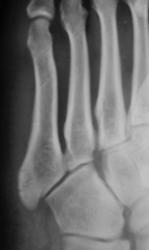

Травма.  Пациент направлен на рентгенографию стопы.

Перелом основания 5 плюсневой без смещения?

Похоже.